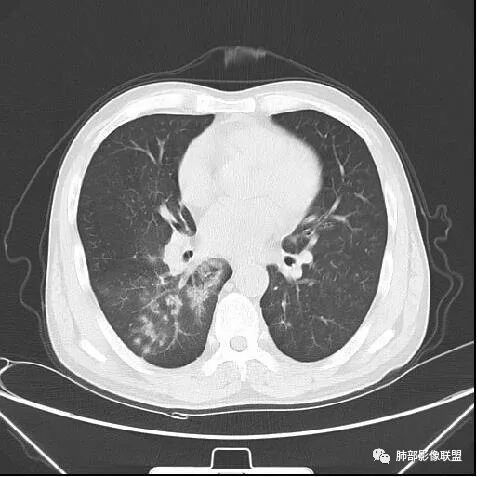

南边:紧贴着斜裂过来的一个病灶,它的特点是:外围大,内带小。它整个下叶背段体积与对侧相比稍微缩小一点,但是缩小地不是很厉害。外支朝前下走了,仔细看血管,肺动脉走行自然,直达远端。远端实变区是肉芽肿成分,稍微有一点低密度,没有明显坏死,稍微有一点点坏死。而且附近有很多卫星灶,附近很多斑片影,有一些明显有气道壁增厚,细支气管炎的特点,还有就是下叶其他段很多斑片状影。换个角度,第一如果是肺癌,刚才看到PET-CT提示肺癌伴阻塞性肺炎,这个是不符合的。第二如果是肺癌阻塞性肺炎,近端血管肺动脉走行不会那么自然集聚的,这个是不符合的。理由是:如果这个病灶是肺癌,那么明显属于中央型肺癌,中央型肺癌的特点是近端大,远端小,近端是一个肿块,远端阻塞,远端阻塞是阻塞性炎症或者不张,它应该体积缩小,斑片状实变,不会这么密实。刚才有老师提到支气管,这个片有缺陷的地方,给的图像好像那层,如果把其他图像拿开再重叠一下。

南边:这个肺门区,11区和7区都有一些淋巴结,淋巴结的形态不是类圆形,而是梭形的。这个病灶给的图比较少,个人倾向,第一强化非常均匀,肉芽肿性病变;第二,里面血管走行非常自然,远端大近端小,倾向炎性,特别是下面还有斑片状影,非阻塞远端,支气管远端病灶下叶背段,其他段也有,所以我倾向炎性;另外,它里面整个走行符合支气管树爬行征,我倾向结核可能,首先我定在炎性,其次有没有结核的可能。

鉴别诊断:肺炎性肺癌,胸膜下起源,外围大,局部占位效应,有膨隆有收缩,这个不太支持。支气管走行里面没有看到支气管进入很自然堵塞的粘液栓的特点。附近这些磨玻璃影,它的磨玻璃影要么边界清楚,要么由内朝外蔓延的,而不是沿着支气管束蔓延的。而且附近斑片状影,有些似乎有结节感,但是大部分不是,它不是我们常见的磨玻璃样结节,有些有,导致像腺泡样结节那种椭圆的沿着血管束分布的,我会把肺炎型肺癌放在待排。

初学者:小细胞肺癌会不会炎症支气管血管束这样淋巴蔓延M-Imaging :小细胞癌转移大,冰冻纵膈南边:按理周围的炎症解释不通飞鹰行动:小细胞没有见过这样没有明显转移的飞鹰行动:阻塞性炎症,结核不好解释,除非有增大淋巴结压迫支气管良孑:外大内小,支气管爬行征,邻近肺野播散灶,TB首选,没意见:多个分支都受累,如果是阻塞,那堵的部位应该在各分支的汇合处,但这例确实没看见Coke with ice:这个人第一感觉是结核。用结核不好解释的就是病灶周围的晕。

右肺下叶背断肿块,外围大,内带相对狭长         远端有膨隆,边缘模糊、凹凸不平         血管走形自然,病灶近端支气管通畅,沿支气管树蔓延         周边有多发病灶,多为磨玻璃密度且边界不清。